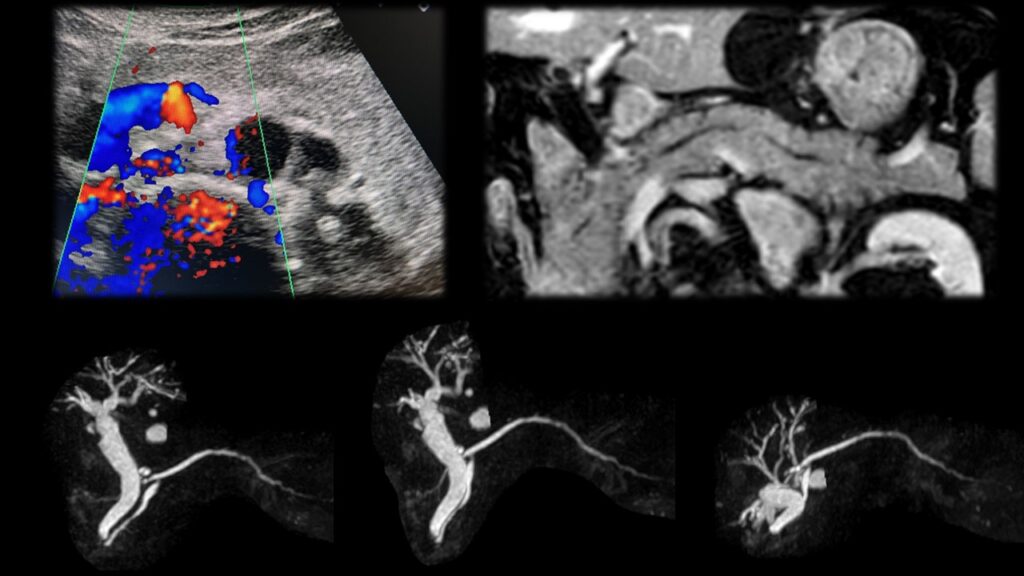

【12月スーパーSALE 15%OFF】 解答・解説】膵頭部腫瘍を指摘された60歳代男性|実践!画像診断 健康・医学の詳細情報

解答・解説】膵頭部腫瘍を指摘された60歳代男性|実践!画像診断。Amazon.co.jp: 見て診て学ぶ膵腫瘍の画像診断 : 大友 邦, 木村。症例1:診断と解説。質の高い『膵臓がん検診 (ドック)』のすすめ -うまい秘訣は。「膵腫瘍の画像診断 : 見て診て学ぶ」木村 理定価: ¥ 12000目立つ汚れなし名前印鑑あり消させていただく予定です!#木村理 #木村_理 #本 #自然/医療・薬学・健康